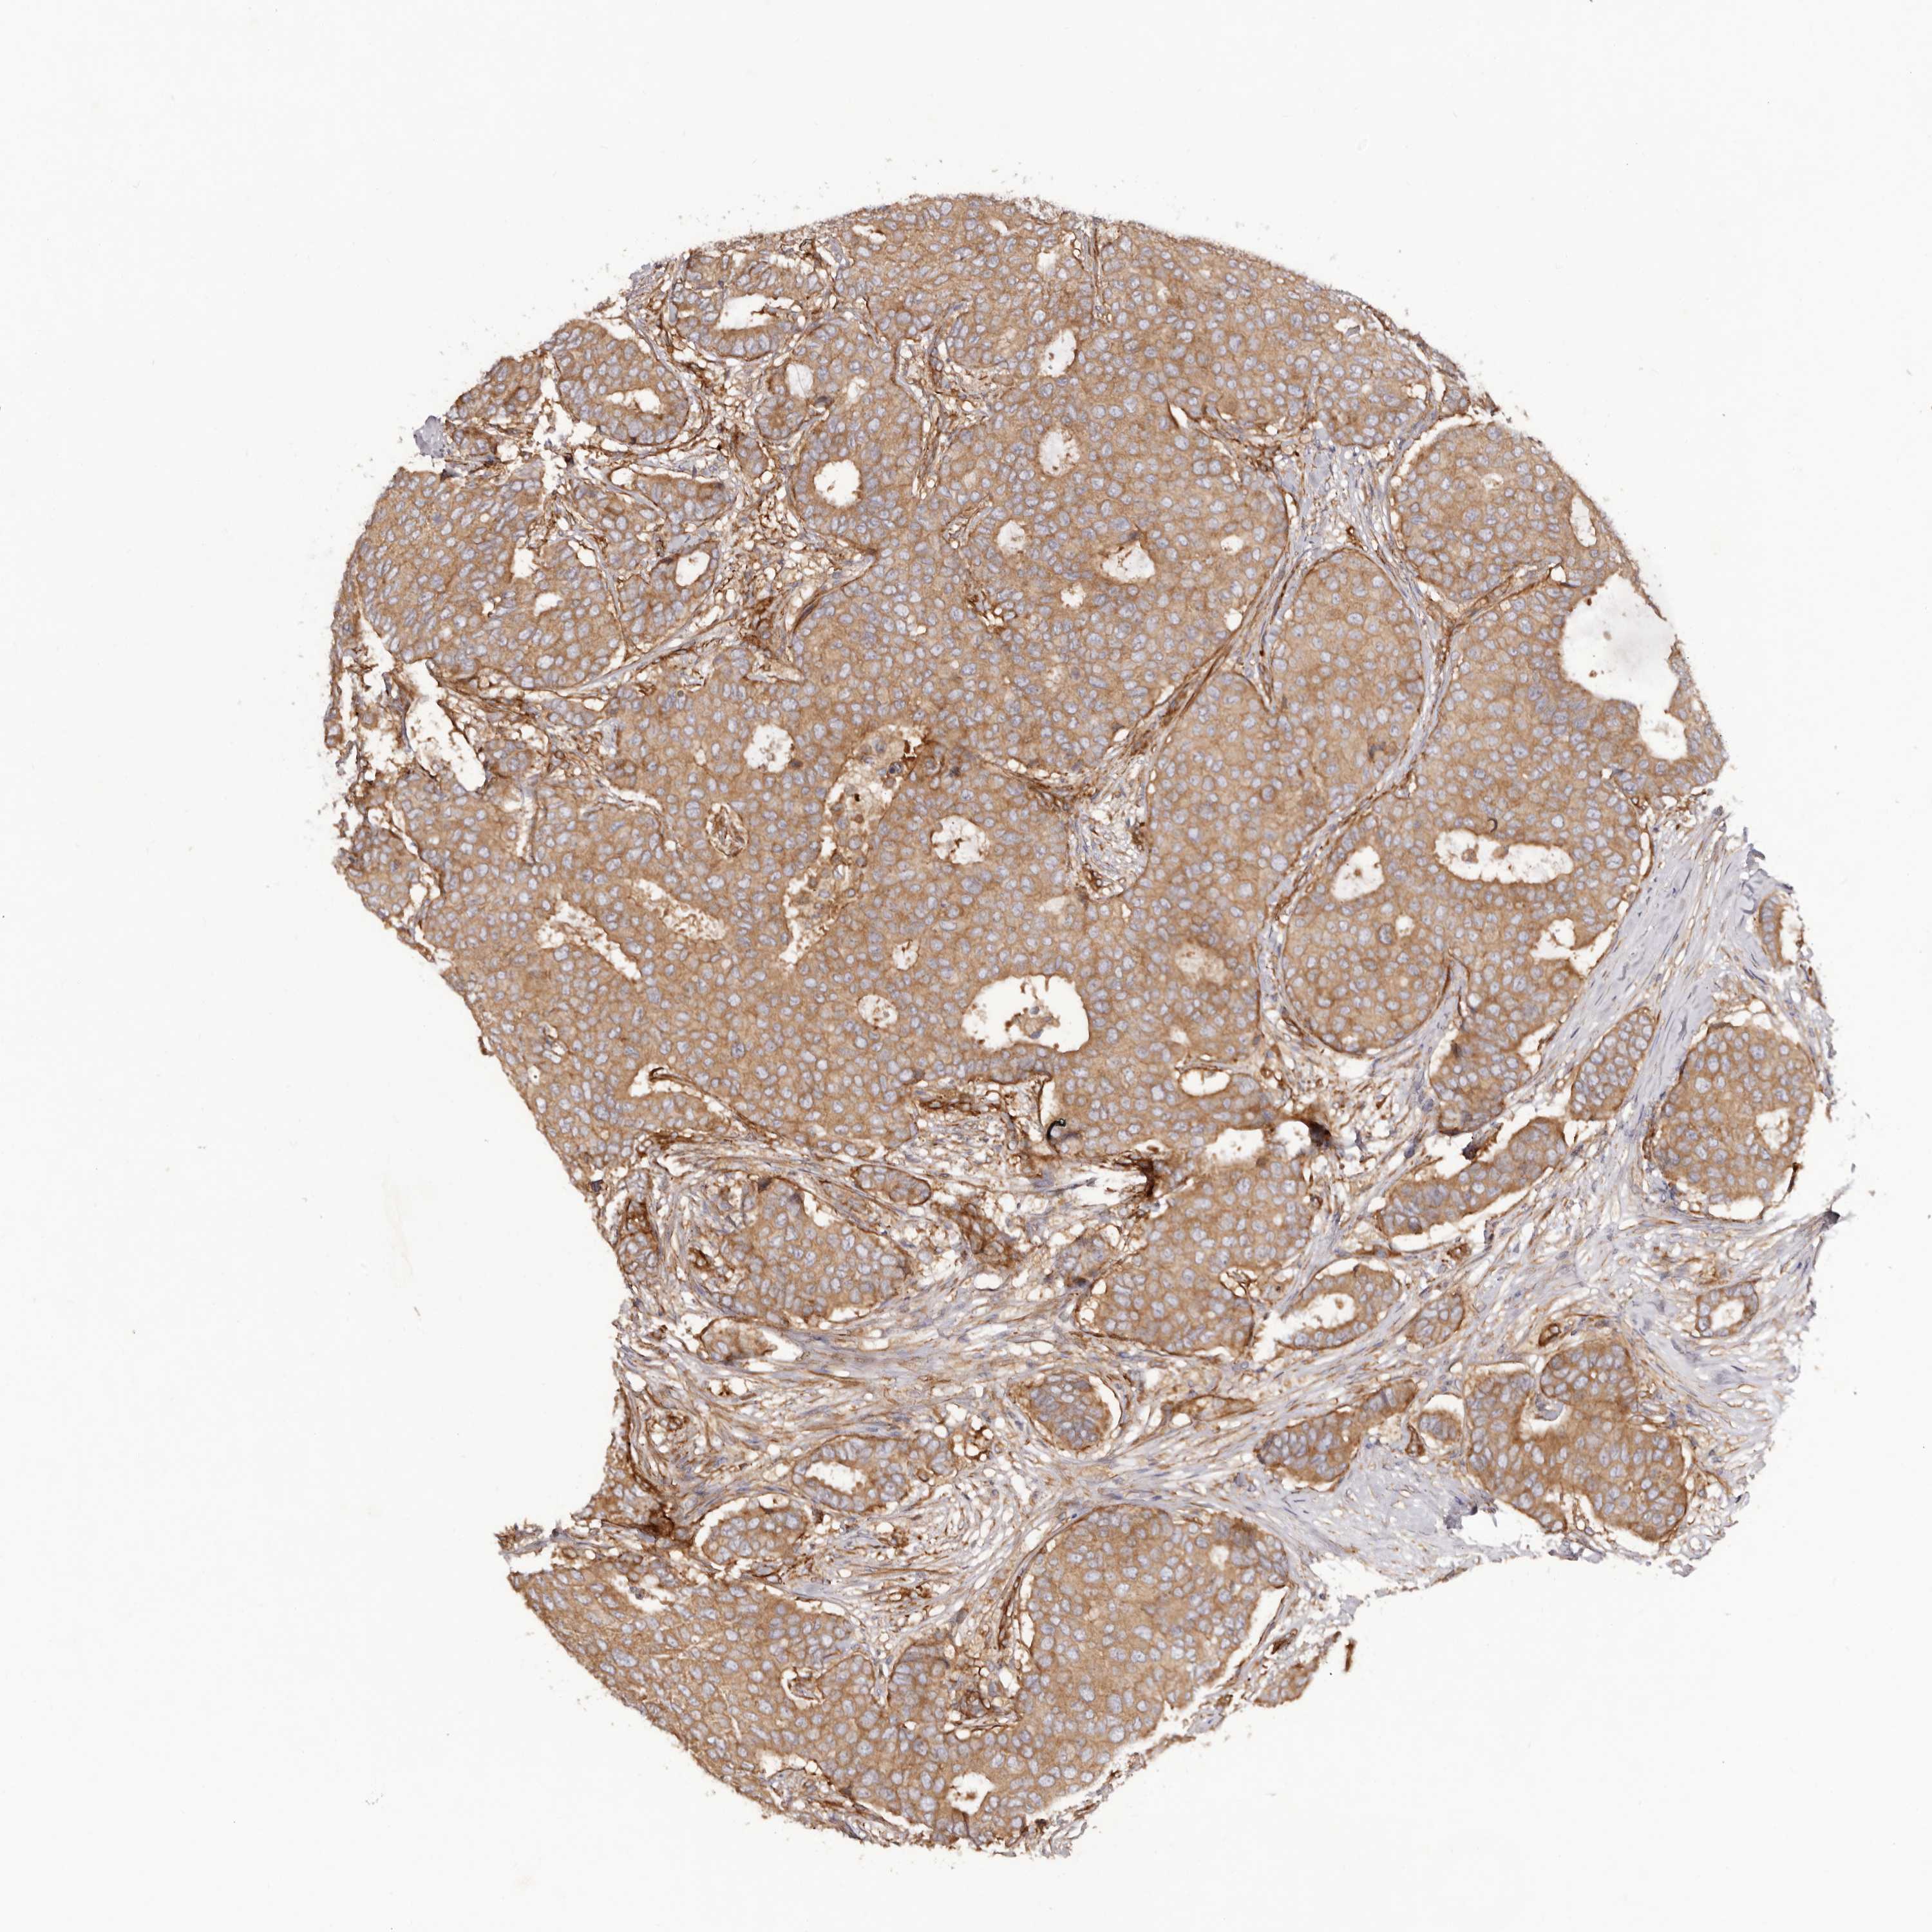

CANCER BREAST CANCER Show tissue menu

BRCA TCGA BRCA VALIDATION PROTEIN EXPRESSION

Breast cancer

Human cancer